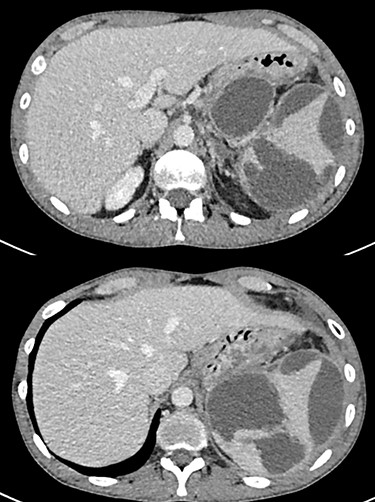

A 26-year-old man with a history of 3 years of excessive alcohol intake was admitted to the emergency department for 48 h of abdominal pain, mainly in the left hypochondrium associated with fever and vomiting. He had a history of 1 year of intermittent abdominal pain that intensified over the last month, which led him to stop alcohol consumption. He was hemodynamically stable upon admission. Laboratory test showed C-reactive protein 176 mg/dl, white cell count 16.7 × 109/L, platelet count 617 × 109/L and serum amylase level 109 U/L. The computed tomography (CT) showed a cystic lesion in the pancreatic tail of 5.7 × 9 cm in size and significant splenomegaly with hypodense areas consistent with a pseudocyst with splenic extension and rupture (Fig. 1).

Pancreatic pseudocyst associated with intrasplenic extension and rupture with subcapsular hematoma.